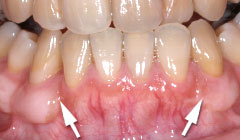

| 歯茎にプラーク(歯垢着が)と歯石の沈認められます。歯肉が腫れ、出血がありました。 | 歯科衛生士の治療と、ブラッシング技術の向上により、歯茎が引き締まり健康的な状態になりました。 | |